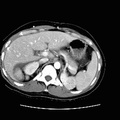

RADIOLOGY: ABDOMEN: Case# 33027: CARCINOMATOSIS. 80 year old female with history of umbilical herniorraphy and abdominal distention. 1) Large amount of ascites with multiple peritoneal based masses as described above. The appearance is consistent with peritoneal carcinomatosis from an as yet undetermined source. The differential diagnosis would include ovarian carcinoma, adenocarcinoma of the gastrointestinal tract, carcinoma of the breast, and renal cell carcinoma. There is apparent metastasis to the umbilical hernia site as well as to a 2 cm right inguinal node. 2) Small bilateral pleural effusions, right greater than left. 3) Simple left renal cyst.